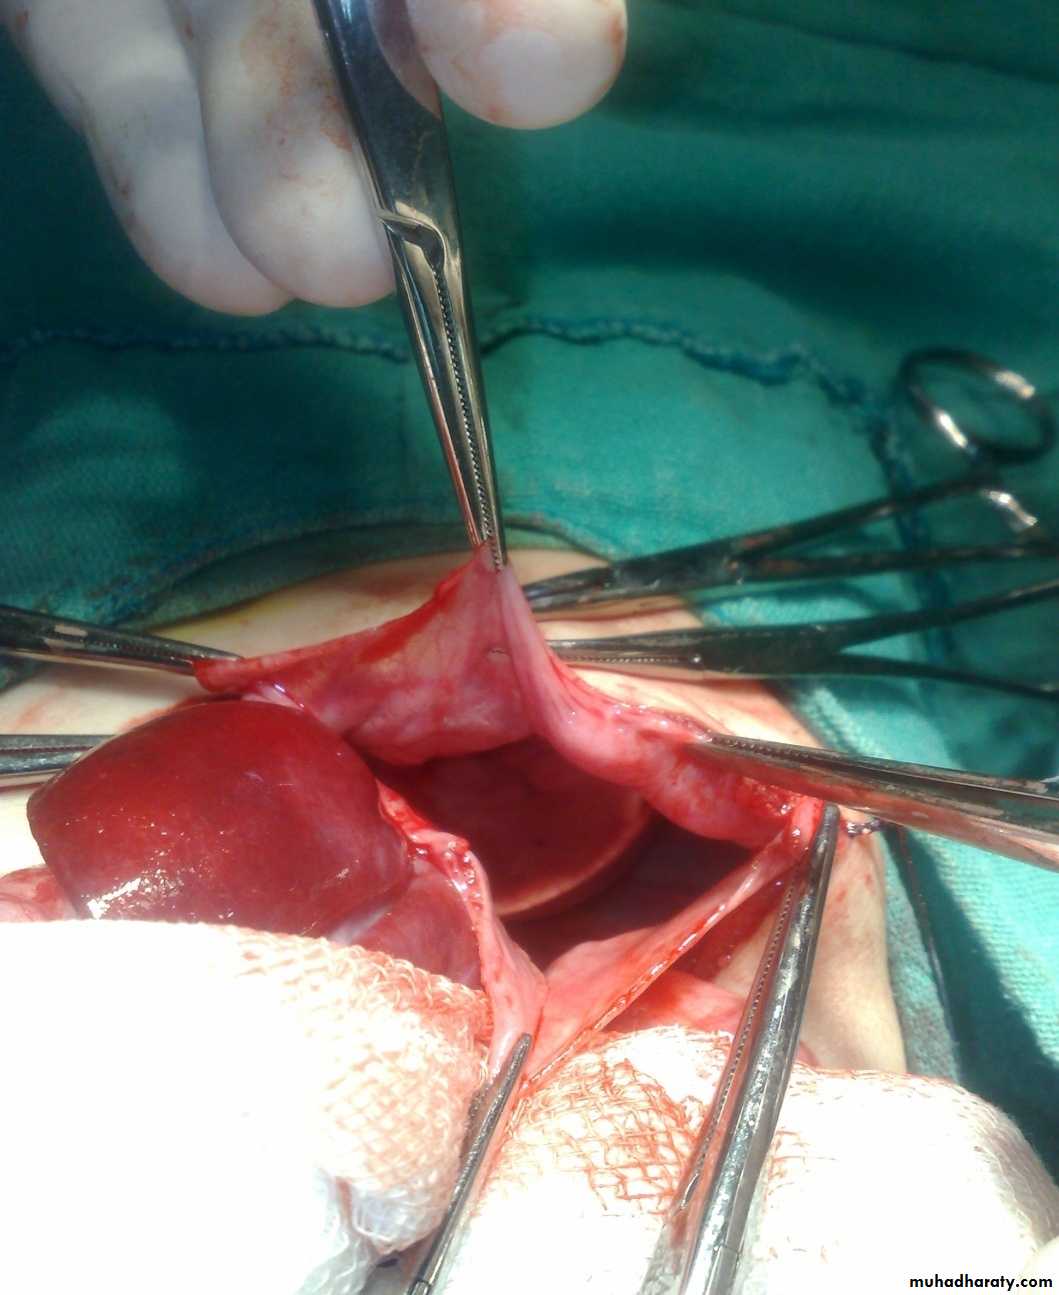

Subcostal incision